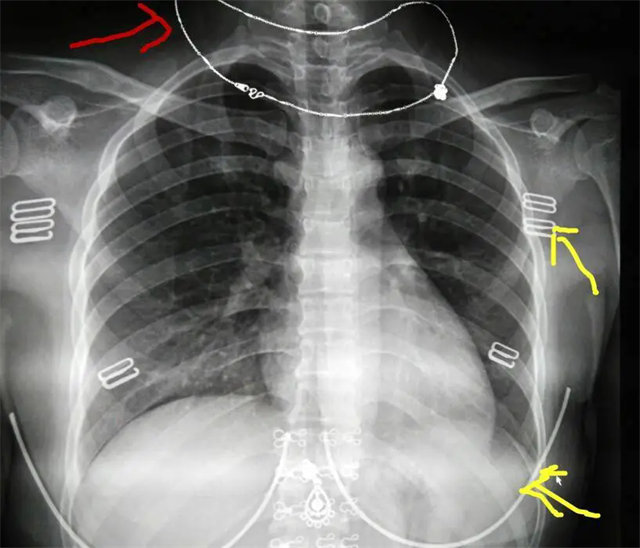

缺陷:肩胛骨未完全拉离肺野,吸气不完全,存在金属伪影遮挡,略有耸肩,且肺尖显示不好,图像颗粒感较强,管电流量不够,信噪比偏低。

解决:去除金属物品后,按标准体位,使患者双肩旋前与前胸一并紧贴成像件,适当调高mAs,然后深吸气后屏气曝光。